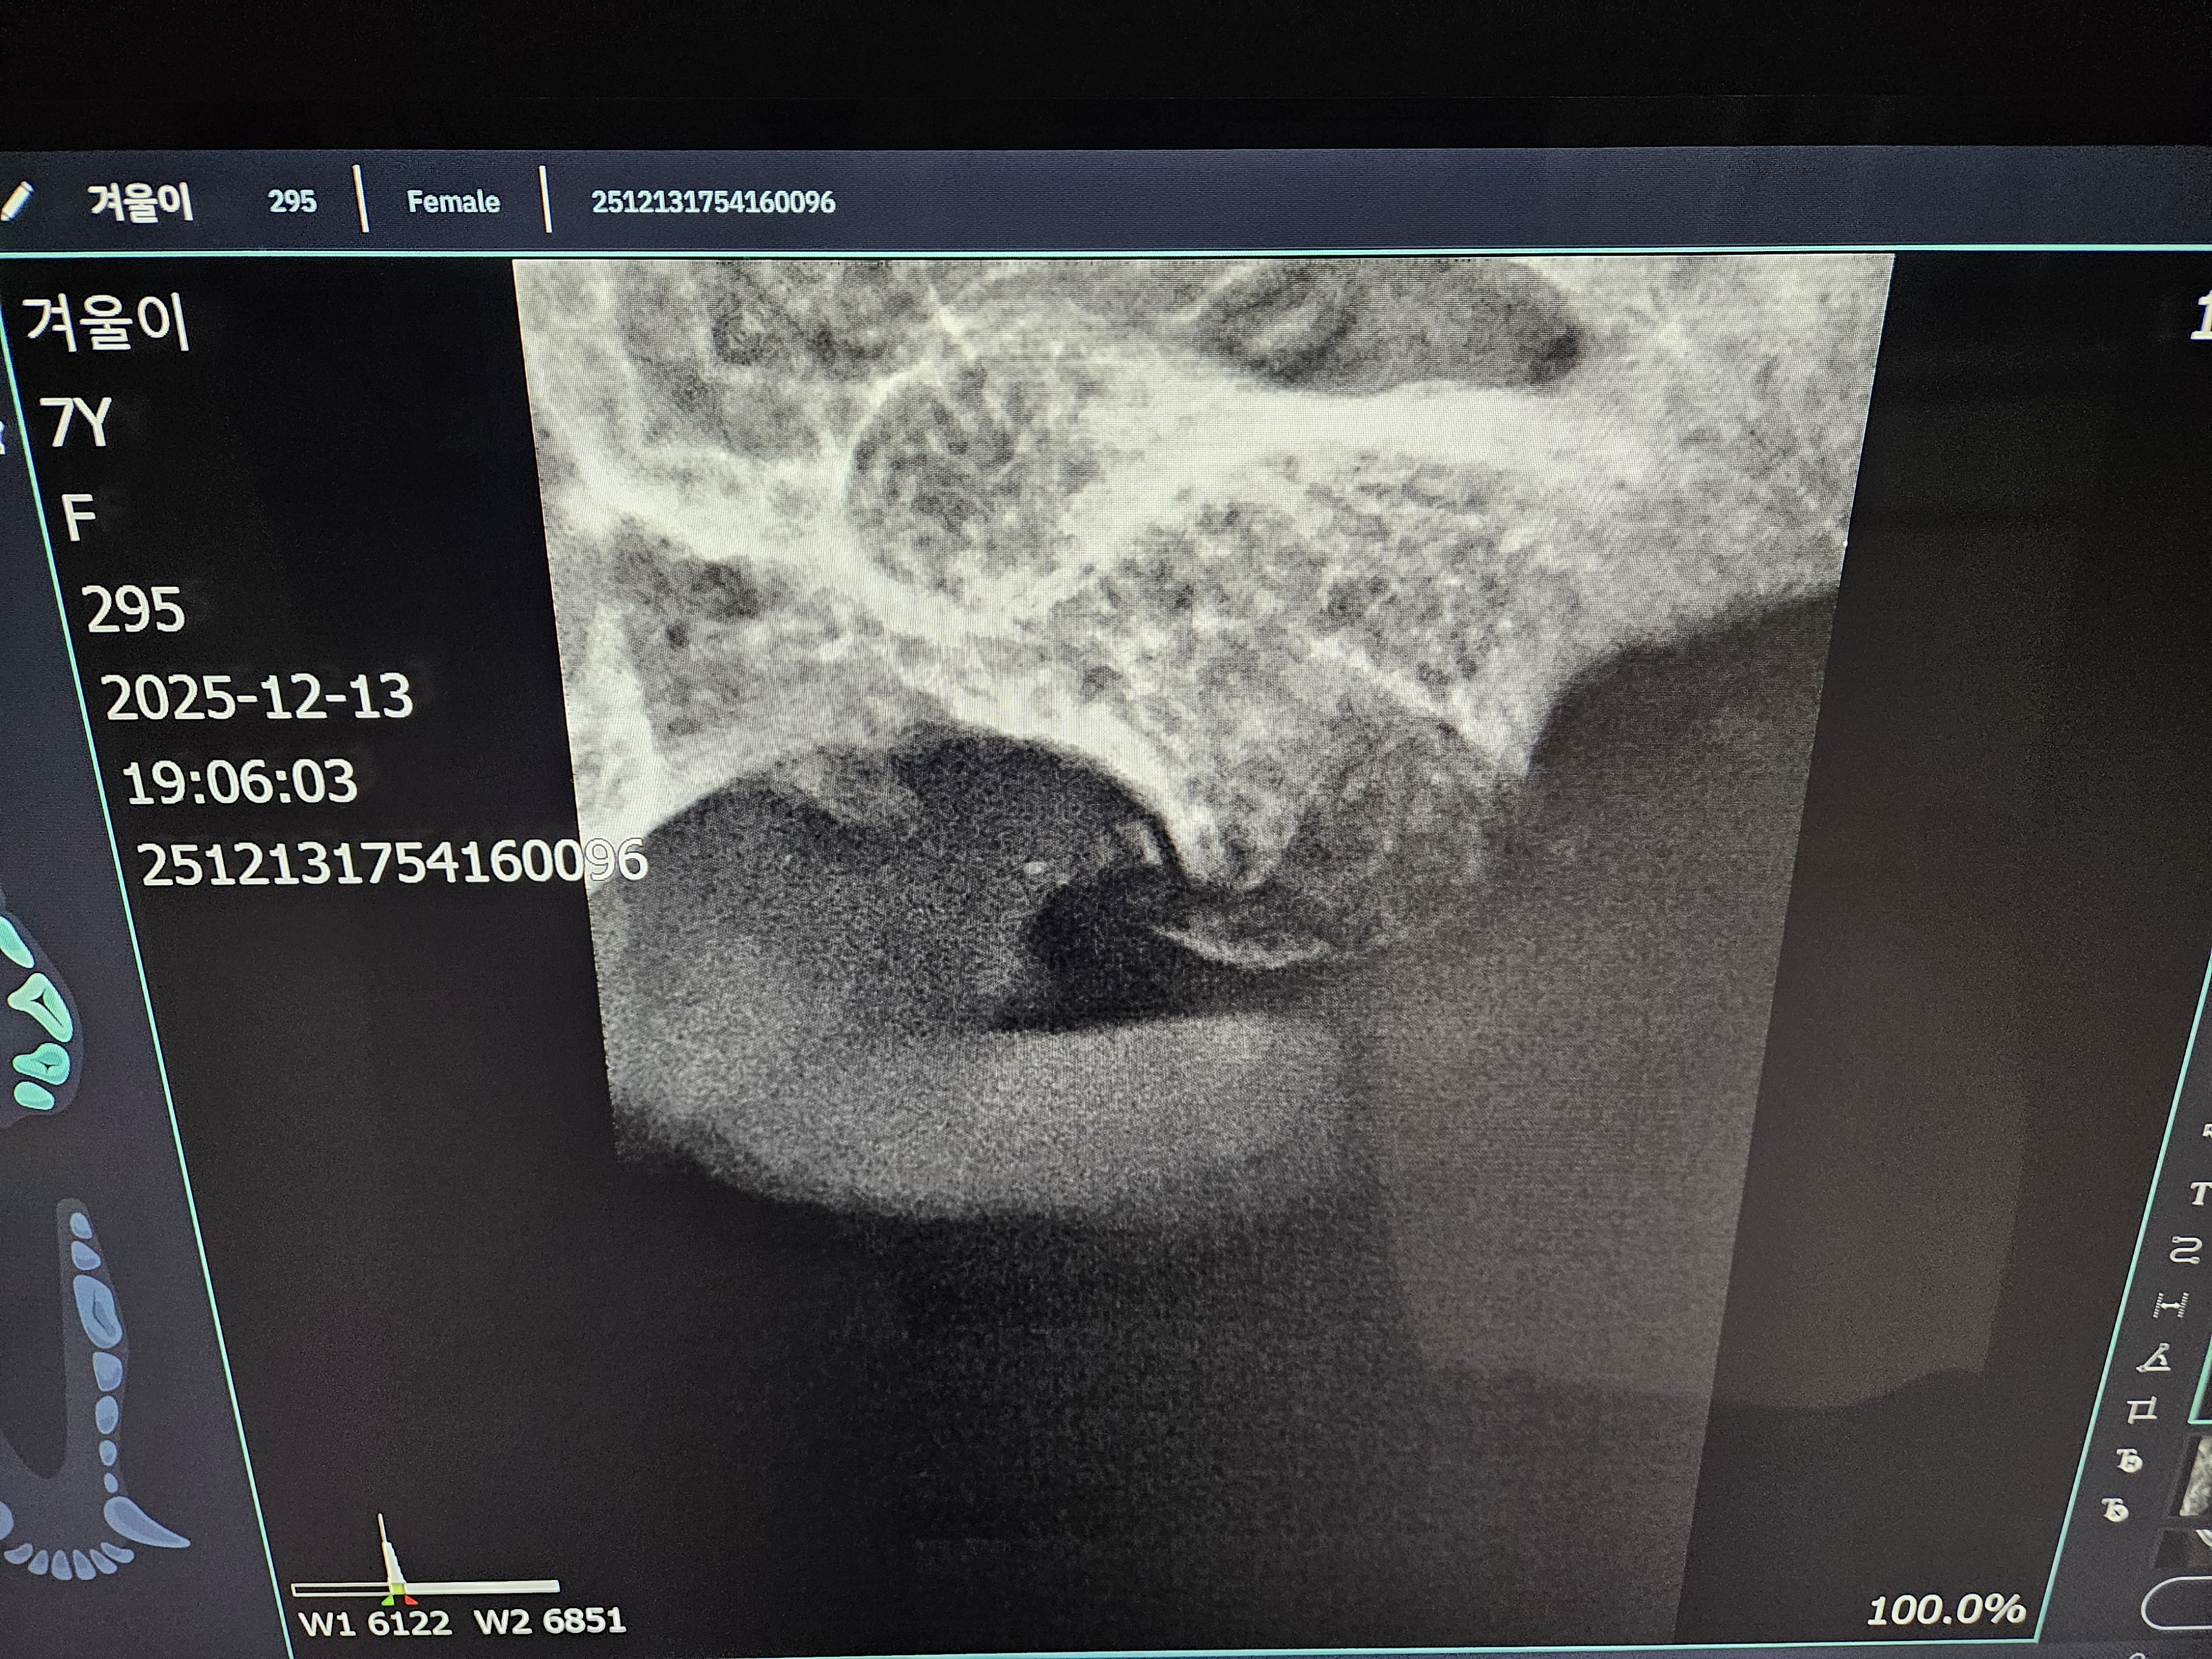

*치아 엑스레이 사진 입니다.

| 치료과정 | 겨울이 염증 수치가 엄청 높았습니다. 보통 정상 수치가 5까지인데 109정도로 엄청 높게 나왔다고 합니다. 염증 수치 같은 경우는 단점이 어떤 부위에 문제가 있는지를 나타내는 수치는 아님. 그런데 겨울이는 구강 안쪽이 엄청 빨개졌었음. 그래서 구내염에 의한 급성염증 수치라고 생각하면 되고, 마취 전에 한 검사는 간수치랑 신장 수치를 체크해주셨는데 콩팥이나 다른 부위는 기능이 정상이라고 하셨습니다. 겨울이 같은 경우는 밥을 잘 못먹었을 뿐이지 간수치나 신장 수치는 특이사항이 없다고 하셨습니다. 겨울이가 입원한 날 빈혈이 너무 심해가지고 수액을 맞았습니다. 그런데 적혈구 개체수도 부족해서 계속 수액을 맞을 수가 없었습니다. 혈액의 적혈구가 부족한혈액이 점점 많아지는 거예요. 항생제 수액으로 마무리 했다고 하셨고,급성 염증 수치는 시간이 지남에 따라서 무조건 좋아진다고 하셨는데, 약은 항생제와 염증 가라앉히는 소염제를 처방해준다고 하셨습니다. 치아 엑스레이 찍은 결과 치조골이라고 해서 이빨에 잡고 있는 뿌리가 어 다 녹아 있었고,그래서 이런 부분들이 이빨의 기능을 상실한 채로 그냥 이가욱씬욱씬한 상태로 있었을거고, 그래서 이빨을 뽑아야 하는 상태라고 하셨습니다. 송곳니는 부러져 있는 부위도 있어서 그런 이빨들은 뿌리 안남기고, 제거를 하셨다고 했습니다. 이빨 자체가 약한 상태이고 전체적으로 발치를 다 한 상태라고 하셨습니다. |